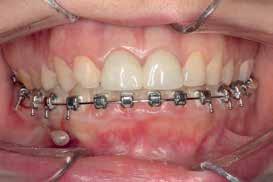

Treatment Progress

February 2021:

Bonding: Genius Passive self ligation ( MEM Corporation, Sweden Taiwan) with 14 NiTi (Thermal ultra) engaged. First molar bondable tube with a built in long extended hook that reached the level of the furcation to apply the force close to the center of resistance of the second mandibular molar.

April 2021:

- 18 NiTi Thermal ultra

June 2021:

- 18*25 NiTi Thermal ultra

July 2021:

- Short head Mini-screw 1.6 diameter, 8 mm length Titanium alloy (Absoanchor®) palced between the mandibular first Premolar and canine at the junction between attached and movable mucosa in a 45 degrees inclination.

- Lower wire: 16x25 stainless steel wire

- Connecting first molar hook to the micro-implant with a chain generating about 200g of force

- To avoid irritation of the cheek when in contact with the miniscrew head, a light cure silicone material was applied to cover the chain and the mini-screw all-together (Softflow®).

For almost 8 months, during the Covid pandemic, the patient was unable to present to the clinic. The work was resumed in March 2022. It was decided then to segment the appliance, including third molar to canine. The 16x25 SS wire was replaced with 17X25 S.S in the lower arch to increase the rigidity of the wire given the short span available.